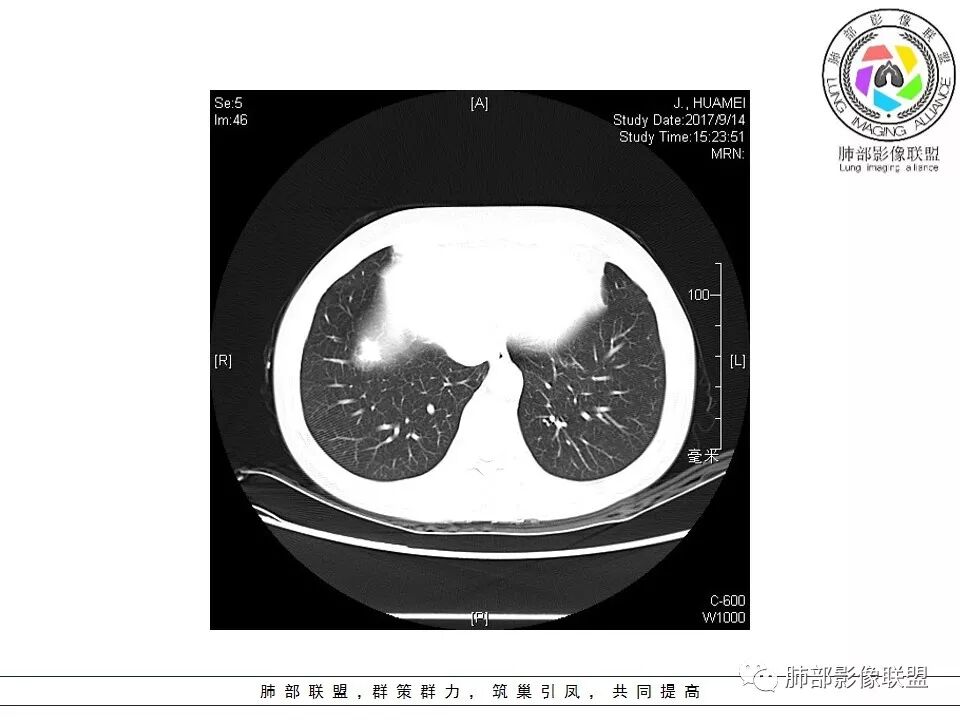

病灶分布:因为肺内淋巴瘤主要侵犯对象是肺间质和支气管黏膜下组织,病灶主要位于在沿支气管血管束分布、肺间质及胸膜下,病灶可跨叶分布

病灶的边缘:有膨隆,浅分叶,也有平直、收缩,平直收缩是因为肿瘤组织浸润致肺泡塌陷及周围纤维组织增生,牵拉正常的肺组织向病灶中心形成聚拢状改变,似呈“炎性”改变。

支气管充气征伴或不伴支气管扩张:肿瘤细胞沿肺间质及支气管黏膜下组织浸润,支气管管壁未见明显破坏,管腔内未见肿瘤细胞充填,呈现充气支气管征;充气支气管走行自然,无扭曲、僵硬,内壁管腔光滑,支气管管壁见增厚并常有管腔的扩张,含气支气管可呈串珠样不均匀扩张,扩张明显处呈空腔样或皂泡样的囊状含气影;支气管扩张目前有两种意见:一是由于肿瘤组织起源于肺间质,肿瘤沿或跨越脏器解剖结构生长,原有解剖结构残留,周围增生的纤维结缔组织牵拉导致支气管扩张;二肿瘤侵犯支气管粘膜下植物神经丛致平滑肌张力丧失;而这类支气管扩张在肿瘤治疗后有时可消失。

间质性改变:多位于病灶周围,可见边缘磨玻璃密度影或晕征及树芽征象,周围组织间质增厚并且有结节感,病理基础为肿瘤细胞浸润细支气管周围间质及肺泡壁。

病例小结:如临床症状轻,肺内多发或单发的结节、肿块及实变,沿血管支气管束、肺间质及胸膜下分布,密度及强化均匀,伴支气管充气征,支气管可扩张,血管造影征,周围有间质性改变,有炎性特点(平直、收缩、周围晕征及树芽),又有肿瘤特点,纵膈及肺门未见肿大淋巴结,没有明显胸膜增厚及胸腔积液,尤其是影像相对稳定,都要想到这个肺黏膜相关淋巴组织淋巴瘤的可能;回顾性分析本病例,还是很符合MALT淋巴瘤影像表现;但是这个患者的NSE轻度升高,使很多群友都想到了小细胞肺癌、类癌的这些神经内分泌肿瘤;神经元特异性烯醇(NSE),是小细胞肺癌、类癌还有其他神经内分泌肿瘤的特异性和敏感性较高的肿瘤标志物,正常值为0-16ng/ml,但是此患者NSE值为17.1ng/ml,为轻度升高;如果在小细胞肿瘤和神经内分泌肿瘤中,NSE是成数十倍的增高,恶性肿瘤的可能性就比较大。如果是轻度升高,诊断神经内分泌肿瘤意义不大,而且里面的支气管充气征伴扩张都不大符合小细胞肺癌和类癌的影像表现。小细胞癌常进展迅速,转移早。